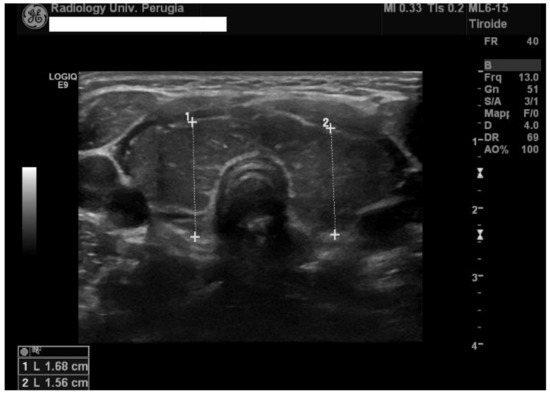

2. Case Presentation